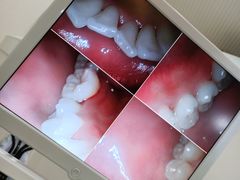

• 永靓口腔.数字化种植矫正中心

• -永靓口腔.数字化种植矫正中心